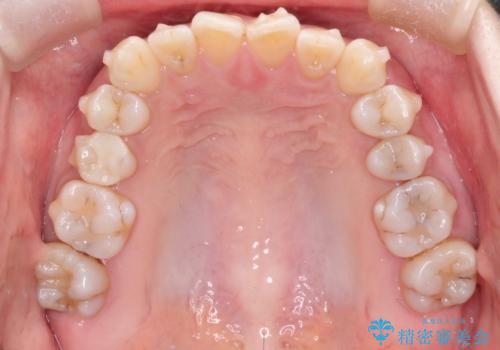

【インビザライン 】前歯の凸凹をなおしたい

- 前歯の凸凹を主訴に来院されました。

インビザライン にて治療を行い、歯並びが綺麗になったと満足していただきました。

前歯のガタガタの量が多かったため、IPR(歯のサイズを小さくするための処置)を行なって治療しました。